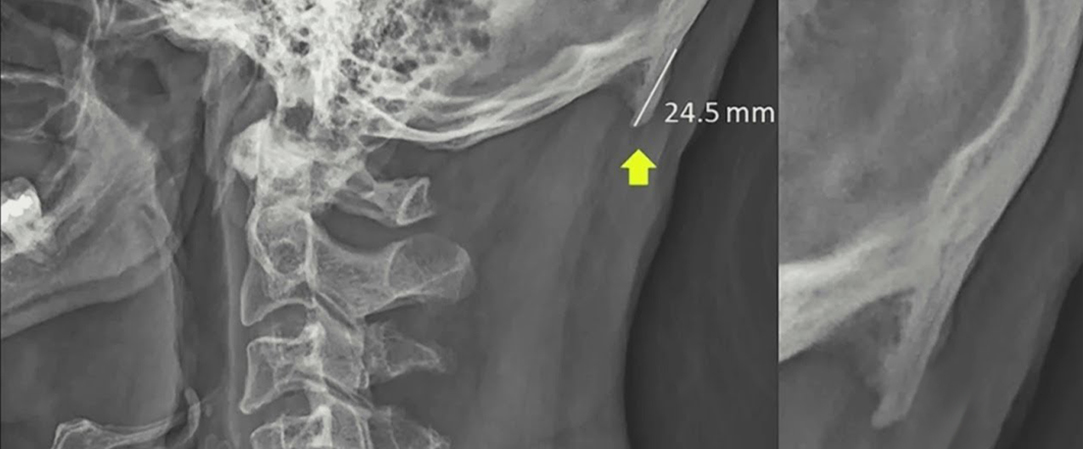

Australští vědci v nedávné studii1 uvedli, že u více než 40% mladých lidí lze v zadní části lebky nalézt zvětšený výstupek (tzv. "týlní ostruhu" angl. occipital spur)

Zjistilo se, že u 41% z nich se vyvinuly 10 až 30 milimetrové kostní výrůstky.

Podle vědců se zdá, že abnormální růst kosti byl způsoben dlouhodobým excesivním tahem za kost v místě úponu.

Ten vzniká např. při dlouhodobém používání smarfonů, kdy je hlava posunuta dopředu.